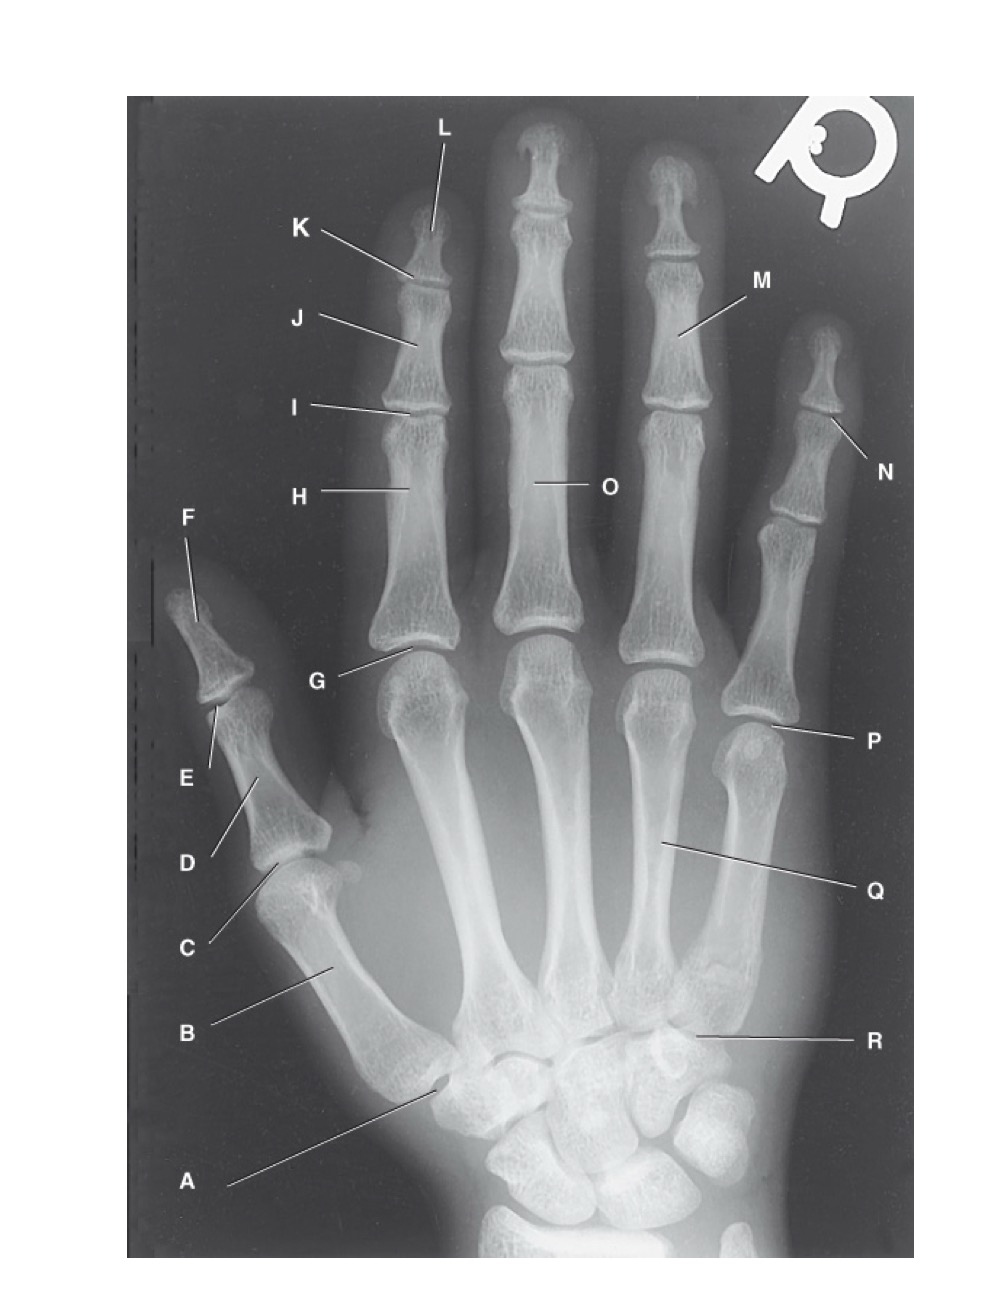

<p>identify A</p>

identify A

first carpometacarpal

New cards

<p>B?</p>

B?

first metacarpal

15

<p>C?</p>

C?

first metacarpophalangeal joint

16

<p>D?</p>

D?

proximal phalanx of the first digit

17

<p>E?</p>

E?

interphalangeal joint of the first digit

18

<p>F?</p>

F?

distal phalanx of the first digit

19

<p>G?</p>

G?

second metacarpophalangeal joint

20

<p>H?</p>

H?

proximal phalanx of the second digit

21

<p>I?</p>

I?

proximal interphalangeal joint of the second digit

22

<p>J?</p>

J?

middle phalanx of second digit

23

<p>K?</p>

K?

distal interphalangeal joint of second digit

24

<p>L?</p>

L?

distal phalanx of second digit

25

<p>M?</p>

M?

middle phalanx of the fourth digit

26

<p>N?</p>

N?

distal interphalangeal joint of fifth digit

27

<p>O?</p>

O?

proximal phalanx of third digit

28

<p>P?</p>

P?

fifth metacarpophalangeal joint

29

<p>Q?</p>

Q?

fourth metacarpal

30

<p>R?</p>

R?

fifth carpometacarpal joint